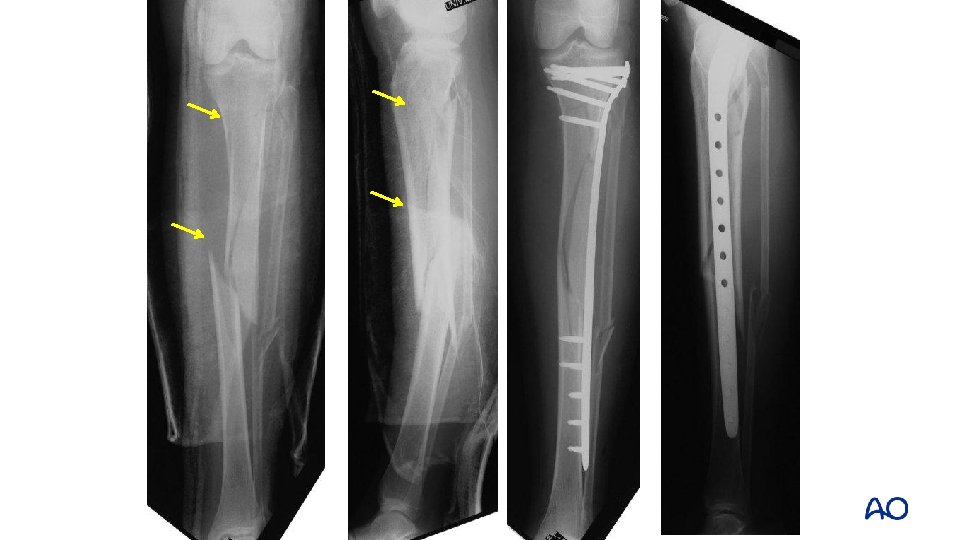

Deformity with distal fractures • Malalignment is common with distal fractures • Vallier: 23% (>40) • Freedman: 8%

Reduction aids for distal fractures • Pointed (percutaneous) clamps • External fixation • Steinman pin • Fibular fixation • Blocking screws

Benefits of plates for distal fractures • Less malalignment • High union rate Vallier et al (J Orthop Trauma. 2011; 25: 736– 741) Vallier et al, (J Orthop Trauma. 2012; 26: 327– 332)